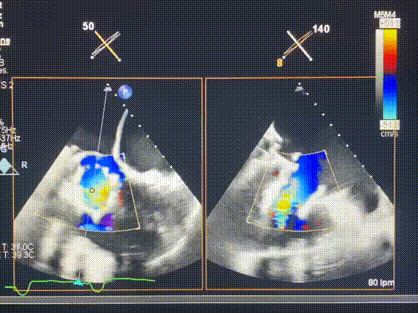

術(shù)中輸送器在超聲引導(dǎo)下調(diào)整位置

手術(shù)在全麻狀態(tài)下進(jìn)行。術(shù)者采用經(jīng)右側(cè)頸靜脈入路的方式將輸送器送入患者心臟內(nèi),在TEE及DSA引導(dǎo)下調(diào)整輸送器頭端角度,使得輸送器與三尖瓣瓣環(huán)平面垂直。在輸送器進(jìn)入右心室后釋放室間隔錨定裝置,而后釋放瓣葉夾持件(2個(gè)耳片結(jié)構(gòu))成垂直狀態(tài)。在TEE及DSA確定夾持件固定至三尖瓣葉根部且位于右室側(cè)后釋放人工瓣心房側(cè)盤片。隨后調(diào)整瓣膜同軸性以及室間隔錨定件位置(貼合室間隔),前推藏針管并固定,進(jìn)而釋放室間隔錨定裝置,并再次確認(rèn)瓣膜位置、穩(wěn)定性及同軸性,合攏輸送鞘后撤出輸送器,完成LuX-Valve Plus人工三尖瓣瓣膜的植入,僅殘余微量瓣周漏。且經(jīng)手術(shù)中心電生理團(tuán)隊(duì)評(píng)估,病人的起搏器和ICD功能沒(méi)有受到影響。